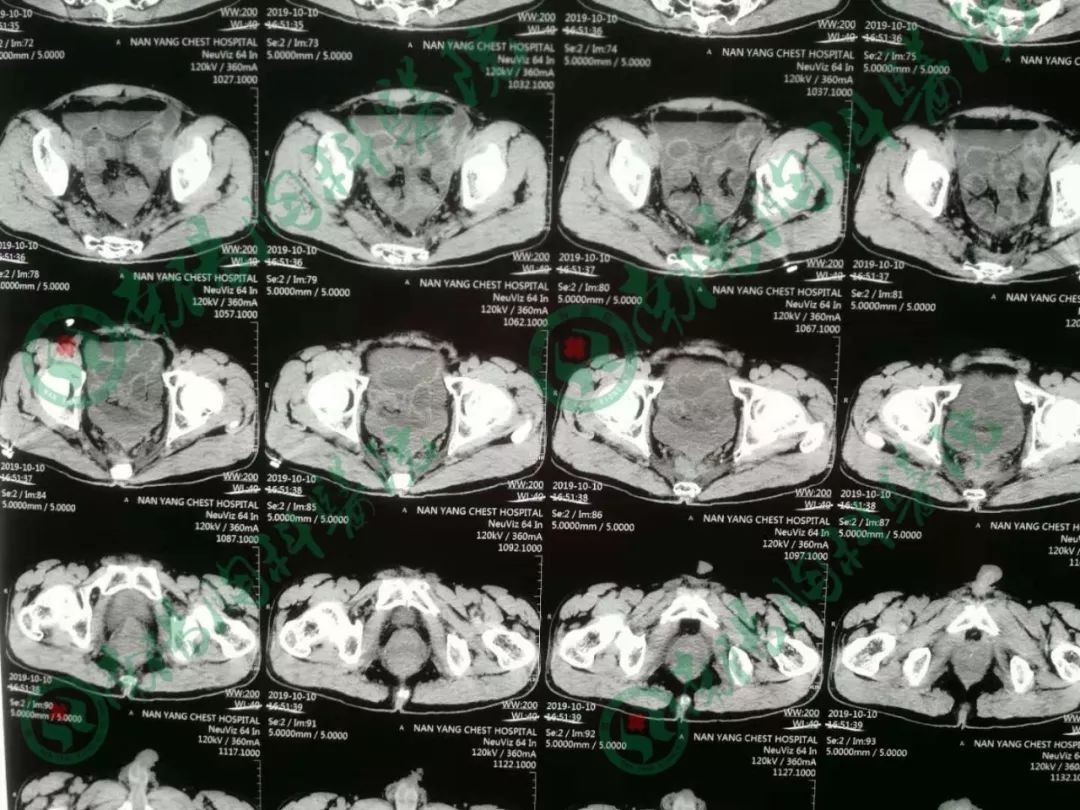

患者经过立位DR和CT检查均提示肠管高度扩张,多发阶梯状液平,病情非常棘手。

告知急诊手术,术中探查见小肠高度扩张,末段回肠扭转粘连于盆底骶前,放射性肠炎改变,呈冻结状,部分肠管受压坏死,行末段冻结扭转回肠切除术,小肠造瘘术,术后病人生命体征平稳,安返ICU。